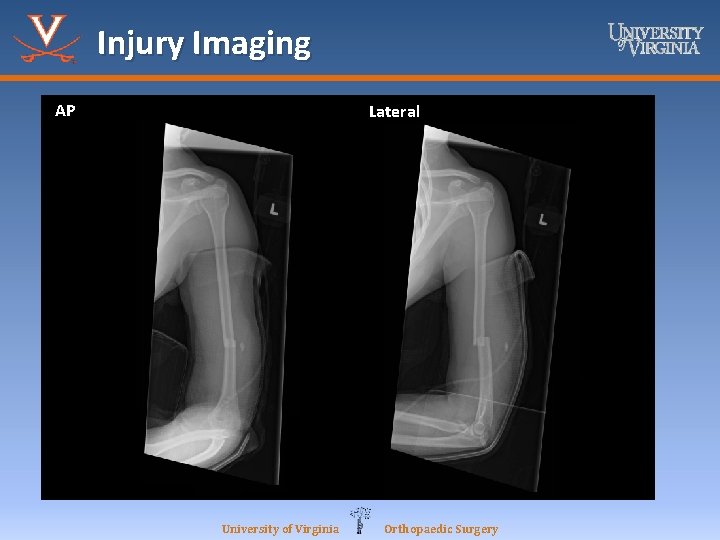

Case Report: M. B. 19 y/o F • M. B. is a 19 -year-old female who presented to the UVA ED as a trauma alert, she was the restrained occupant of a high-speed, rollover MVC. Her orthopedic injuries included: right radial shaft fracture, left humeral shaft fracture, and right forearm laceration with exposed FDS muscle/tendon. • No PMHx or PSHx University of Virginia Orthopaedic Surgery

Case Report: M. B. 19 y/o F • Right Forearm – Right forearm tender to palpation, mild deformity, 6 cm laceration with exposed muscle belly – Intact motor to AIN/PIN/U nerves – SILT M/R/U nerve distributions – Compartments soft and compressible – 2+ radial pulse • Left Arm – No deformities noted, no open wounds – Motor intact to wrist flexion/extension, finger flexion/extension/intrinsics – Intact motor to AIN/PIN/U nerve – SILT M/R/U distributions – Compartments soft and compressible – 2+ radial pulse University of Virginia Orthopaedic Surgery

Injury Imaging AP Lateral University of Virginia Orthopaedic Surgery